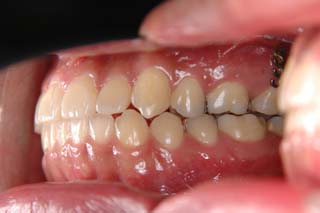

(叢生/顎関節症/上顎左側小臼歯抜歯)

左側の臼歯部干渉が、治療を通じてみられたので、オーバーコレクション気味に軽い臼歯部開咬にしてあります。咬合器上での顎位の偏位はかなり軽減し、頭頚部の症状も随分軽快したようです。歯列の改善と、顎関節症状には、なんだかの関連があると推測されますが、不明なことが多いです。